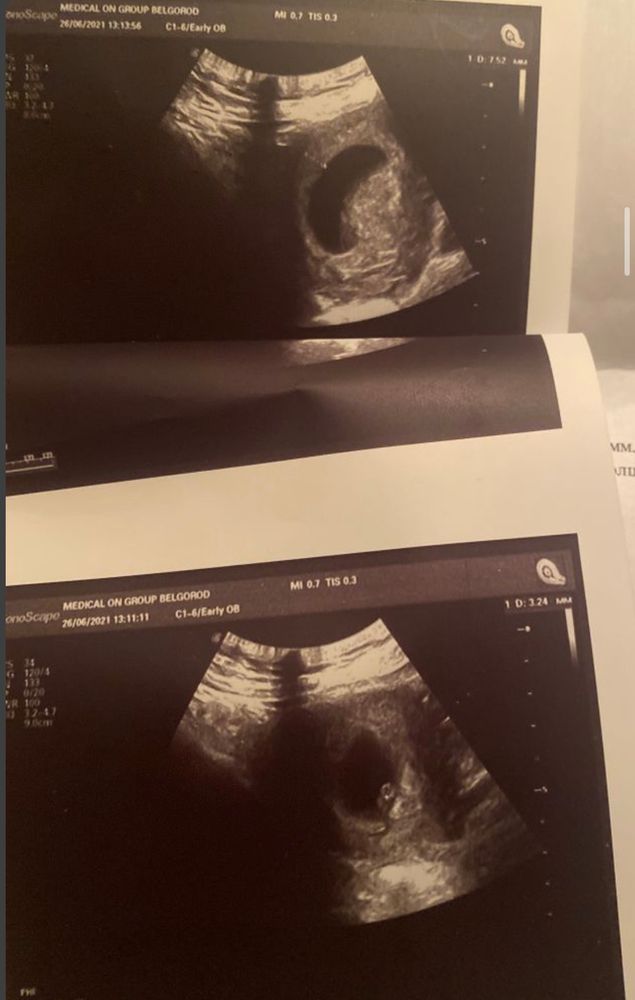

Zvezdochka, у меня в нач берем волнение по этому поводу было.. И немного сомнений осталось. На последнем узи, в 7 недель один эмбрион, 1 желточный мешочек, но ПЯ странной формы.. Ставят тонус матки, но живот не тянет вообще.. Боюсь, если 2-е окажется.. Старший сын(5л) с шилом в попе..

Zvezdochka, это с разных ракурсов Изображение